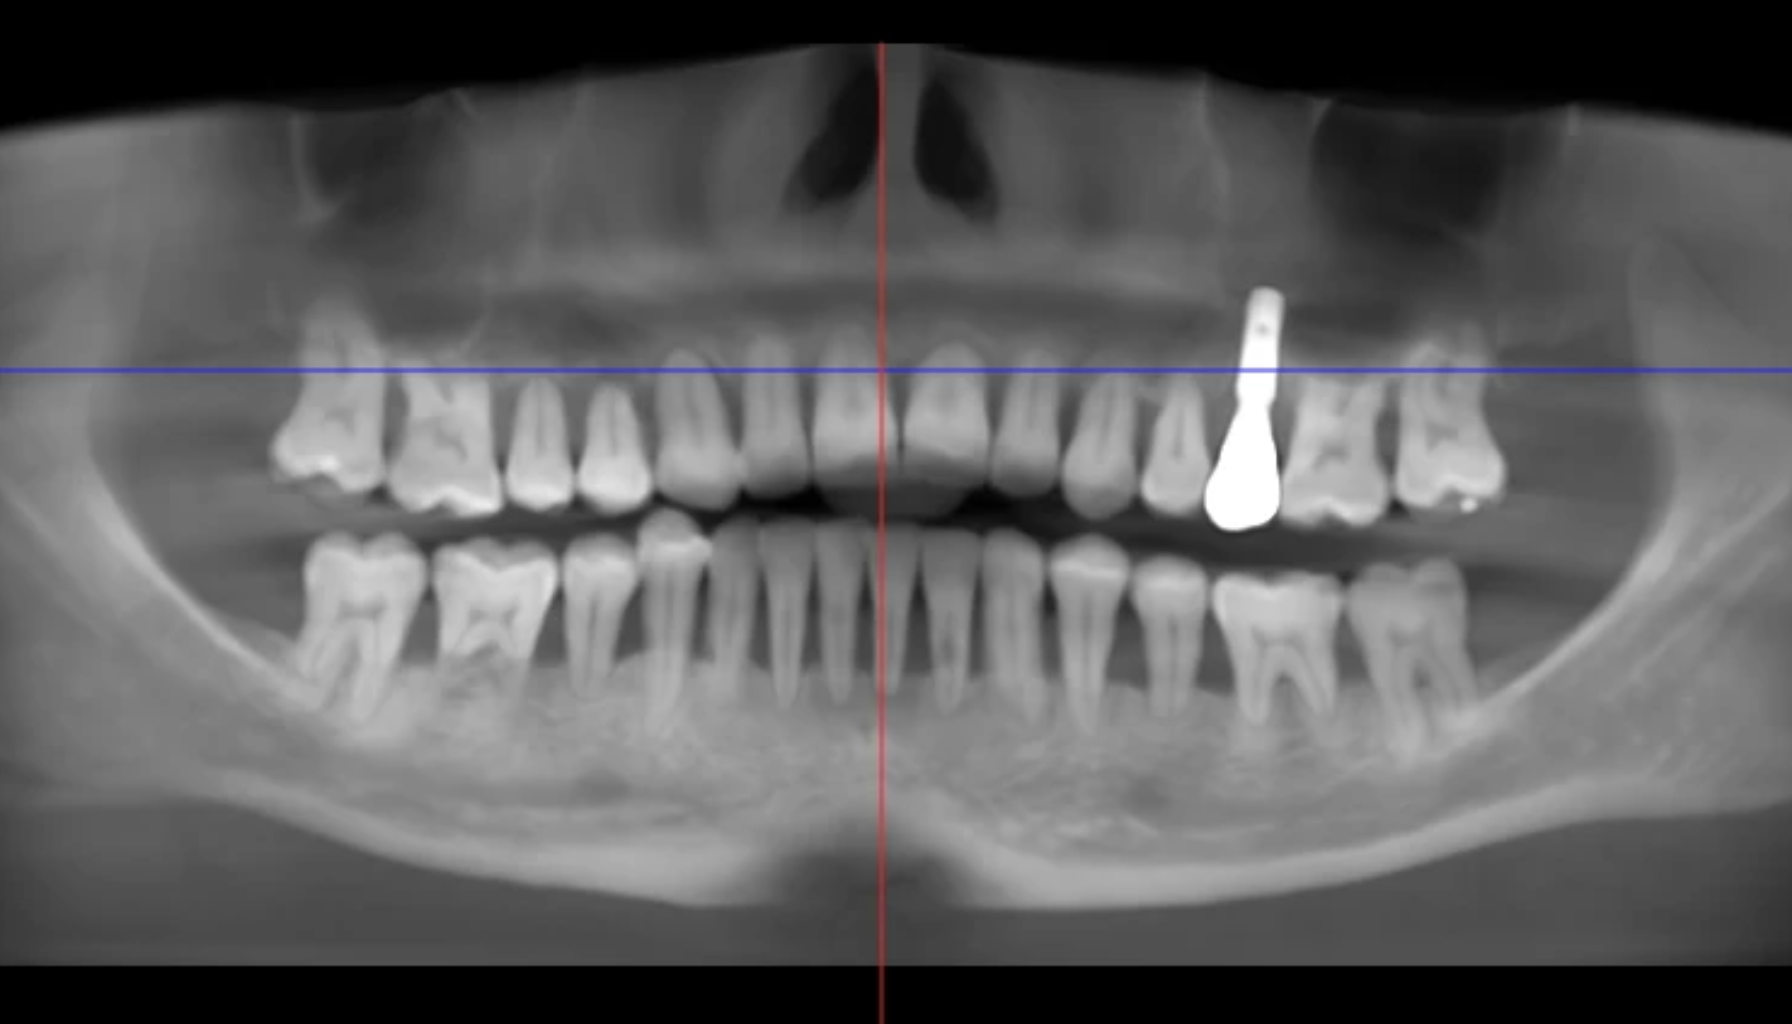

Det finnes to hovedtyper: intern resorpsjon, som starter inne i tannens nervekammer, og ekstern resorpsjon, som begynner fra utsiden av roten. Tilstanden kan utvikle seg i skjul og skade både rot og tannkrone.

- Det finnes både intern og ekstern resorpsjon: Intern resorpsjon starter inne i tannen og sprer seg utover, mens ekstern resorpsjon begynner på utsiden – ofte ved roten. Ekstern resorpsjon er mest vanlig og oppdages som regel via røntgen.

Det finnes ulike former – både interne og eksterne – og mange merker ingen symptomer før det er for sent. Tilstanden oppdages ofte ved tilfeldige funn hos tannlegen, gjerne gjennom røntgen.